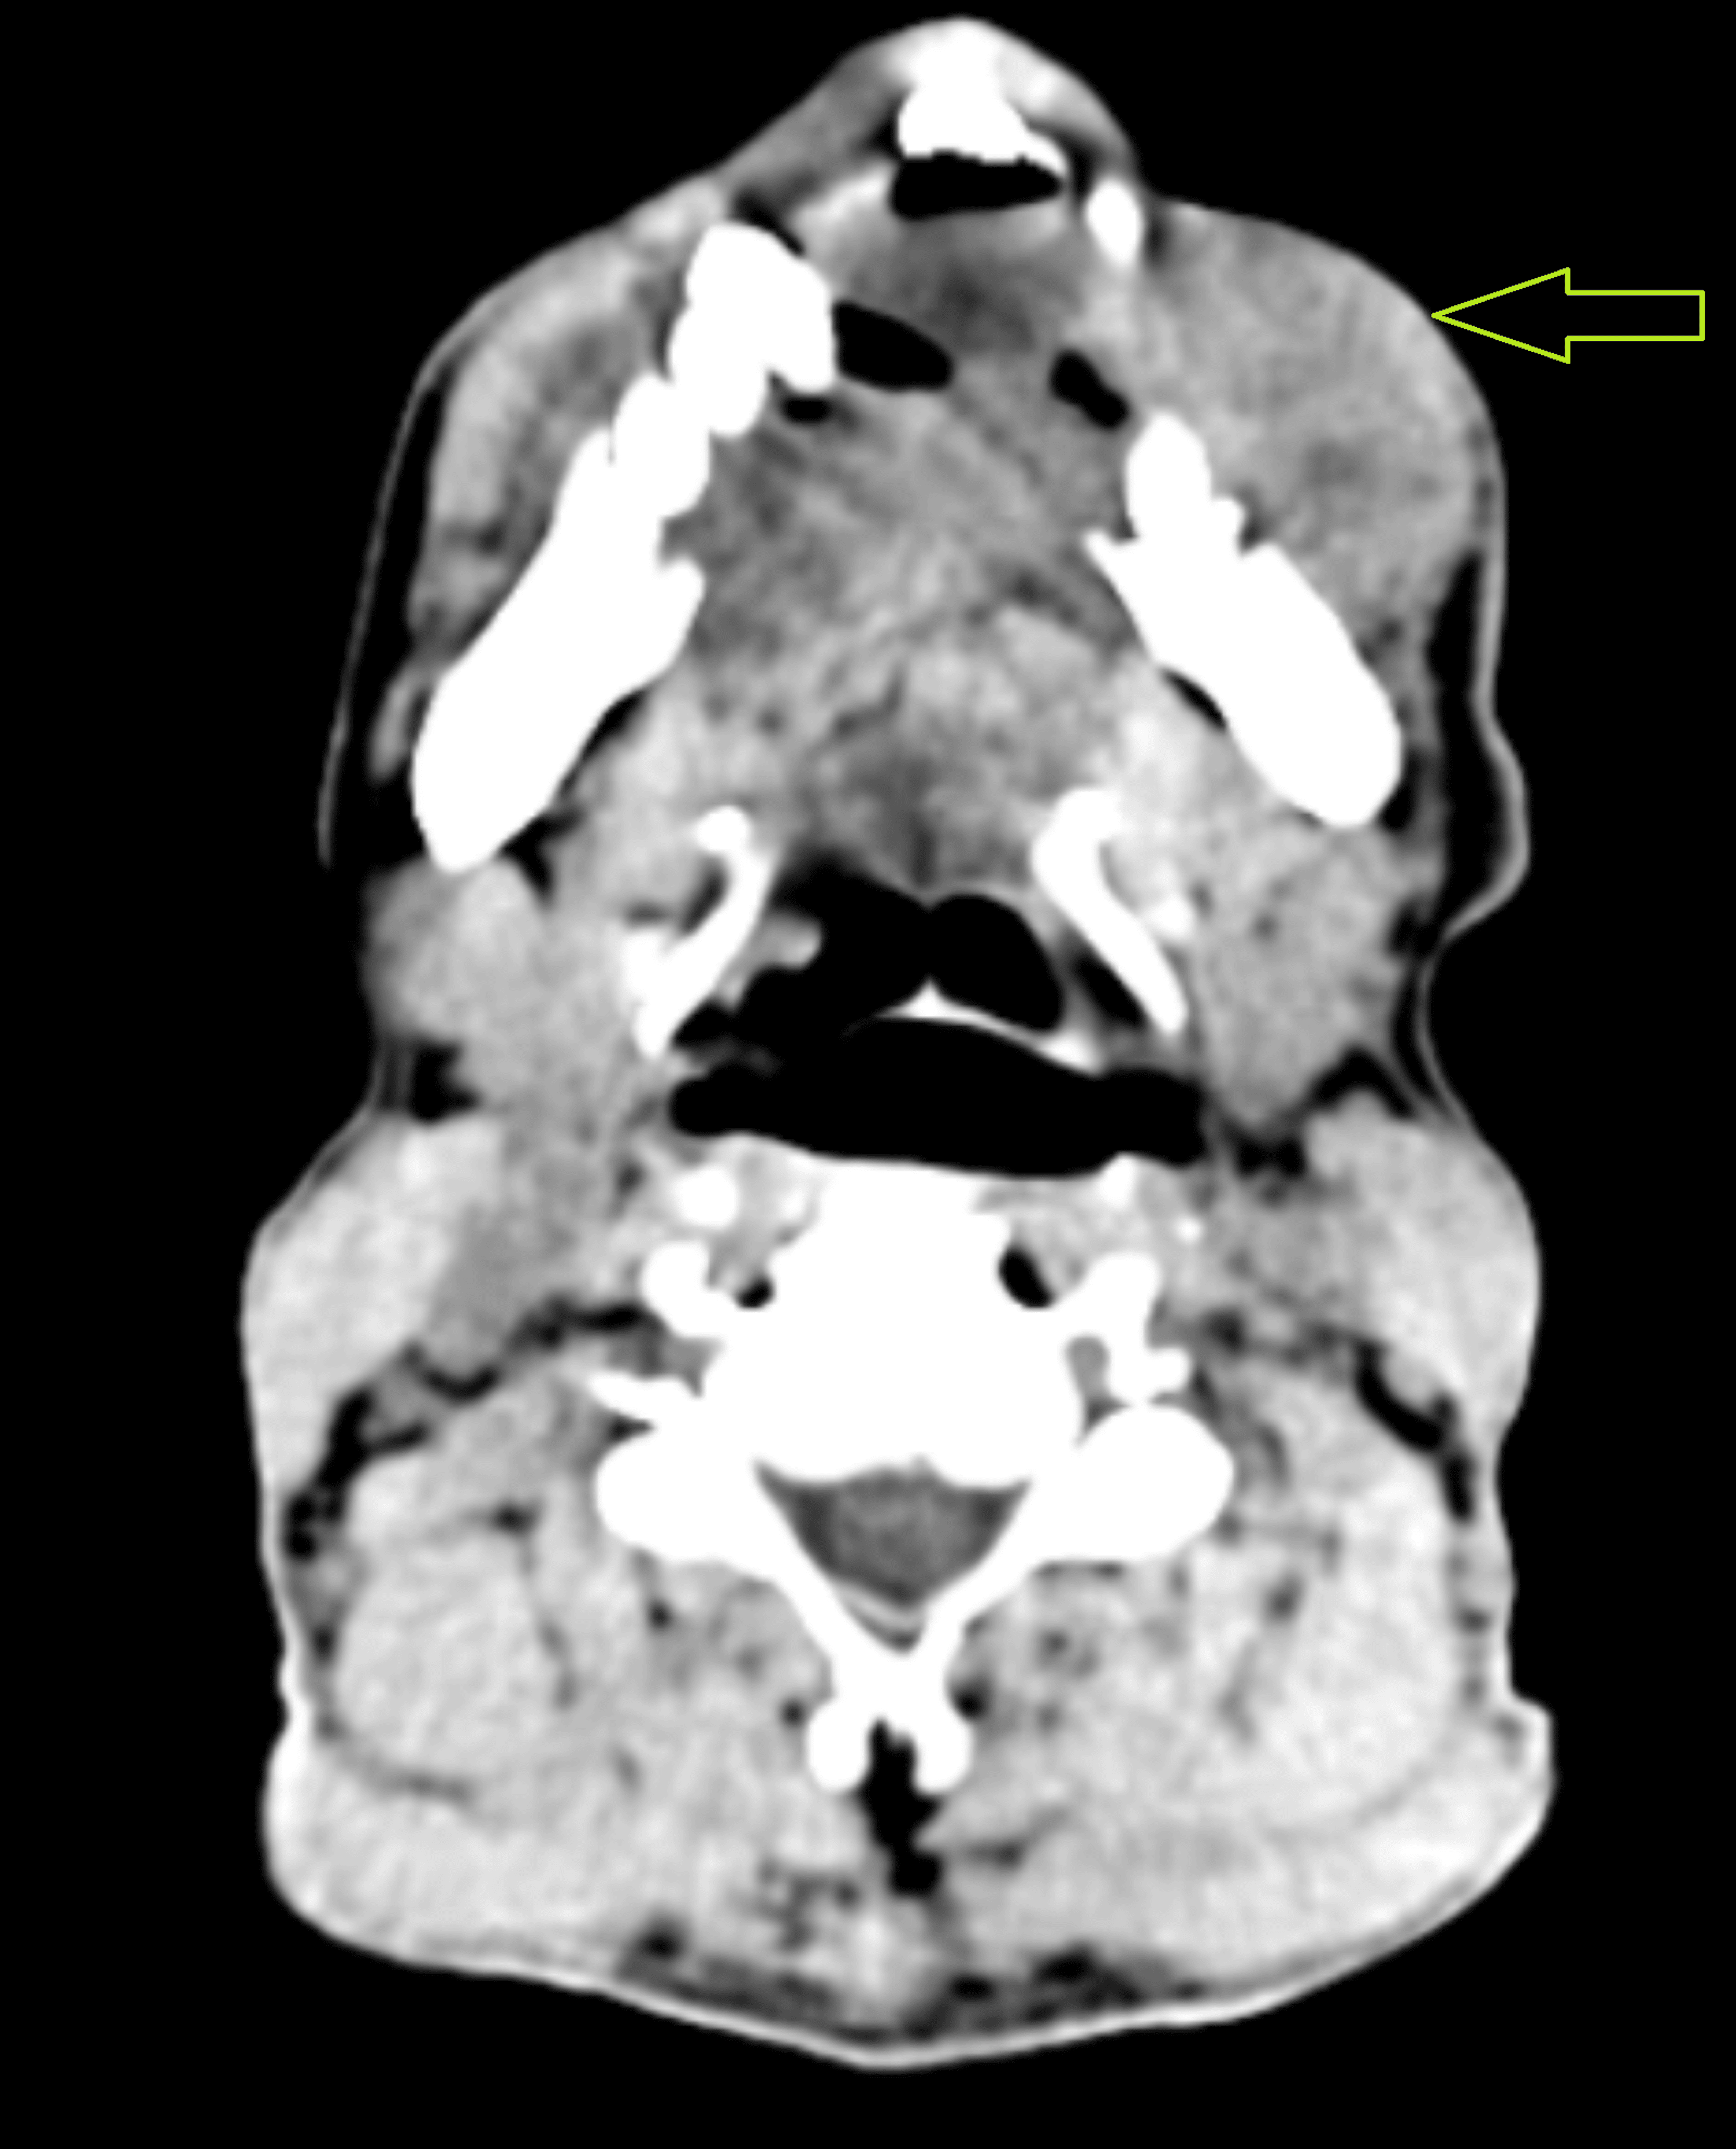

After the initial evaluation, the patient was quickly referred to the oncological surgery section for additional testing. Upon detailed investigation, the individual disclosed a long history of alcohol addiction spanning three decades and tobacco usage lasting 25 years. The area of interest was promptly subjected to a biopsy, and the existence of squamous cell carcinoma was later confirmed by histological examination. A suitable neck dissection, free fibular flap, scalp flap, and segmental mandibulectomy were all planned as part of a composite resection. The patient had no surgical background or comorbidities upon examination before anesthesia. A mouth opening of two fingers and a Mallampati categorization of class IV, indicating limited visibility of the hard palate, were noted during the airway examination. There was restricted temporomandibular joint movement due to an accompanying painful mouth lesion, although neck movement seemed sufficient. All laboratory tests, including the complete blood count, kidney function test, and liver function test, revealed values within acceptable ranges. Contrast-enhanced CT of the neck showed an extraoral fungating mass with no intraoral extension, involving the parasymphysis region, mentalis, depressor labii inferioris, left depressor anguli oris, and left buccinators (Figure 2).